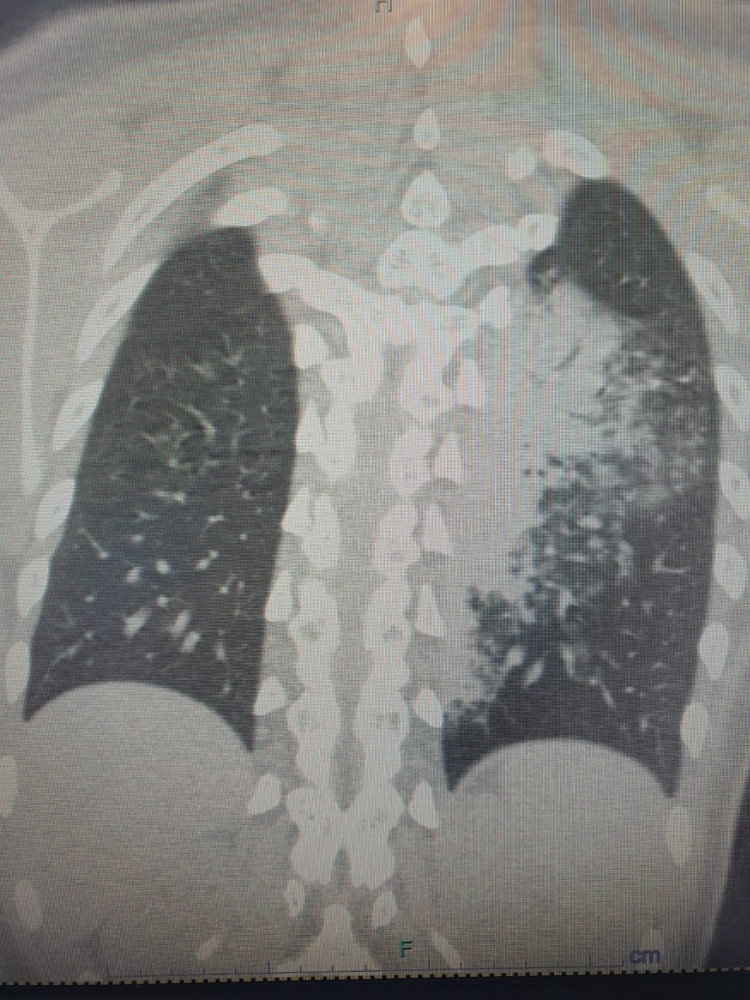

Sıcakların artması ve yaz sezonu ile tatile çıkanların klima kullanımı artarken, bronşit ve zatürre vakaları da hızla yükseliyor. Altınbaş Üniversitesi Tıp Fakültesi Göğüs Hastalıkları Anabilim Dalı Öğretim Üyesi Prof. Dr. Şevket Özkaya, özellikle otel ve tatil köylerinde klima maruziyetine bağlı hastalıkların arttığını ve en çok etkilenenlerin çocuklar olduğunu vurguladı. Prof. Dr. Özkaya, "Legionella" bakterisinin klimalardan üremesi sonucu ortaya çıkan "Lejyoner hastalığı"nın, çocuklarda COVID-19'a oranla daha fazla zatürreye neden olduğunu ve bu durumun şaşırtıcı ve endişe verici olduğunu ifade etti. Prof. Dr. Özkaya, vatandaşların klima kullanımında dikkatli olmaları gerektiğini ve özellikle kronik hastalığı olan kişilerin bu konuda daha duyarlı olması gerektiğini belirtti.

Göğüs Hastalıkları Uzmanı Prof. Dr. Şevket Özkaya, özellikle otel ve tatil köylerinde konaklayan kişiler arasında “beni klima çarptı” diyen neredeyse her iki kişiden birinde bu hastalıkların saptandığını belirtti. Prof. Dr. Özkaya, bu durumdan en çok etkilenenlerin ise çocuk yaş grubu olduğunu vurgulayarak, “Ciddi sayıda, daha önce görülmemiş derecede çocuk bronşiti ve zatürresi vakaları görmeye başladık. Hatta COVID-19 salgınında, çocuk yaş grubunda COVID-19 virüsüne bağlı bu kadar çok zatürre görmüyorduk. Son günlerde; ‘Legionella’ bakterisinin, çocuk yaş grubunda COVID-19’a oranla çok daha fazla zatürreye neden olduğunu görüyoruz” diye konuştu. “Kronik rahatsızlığı olanlarda ölümcül olabilir”